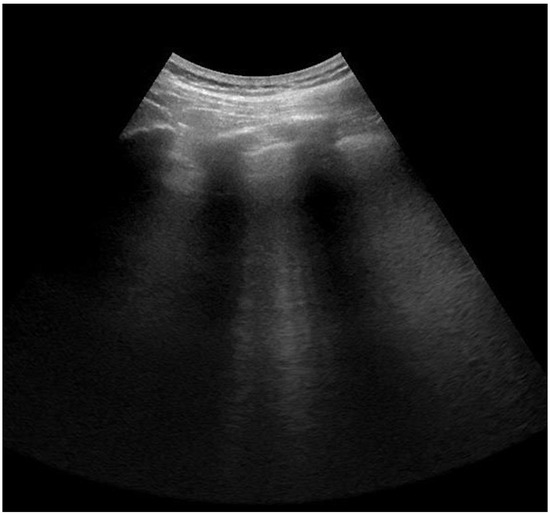

2.4. Lung Ultrasonography and Score Assessment

| Interstitial Edema (B1 pattern) | 35 (92%) | 23 (61%) |

| Alveolar Edema (B2 pattern) | 31 (82%) | 16 (42%) |

| Consolidation (C) | 11 (29%) | 4 (11%) |